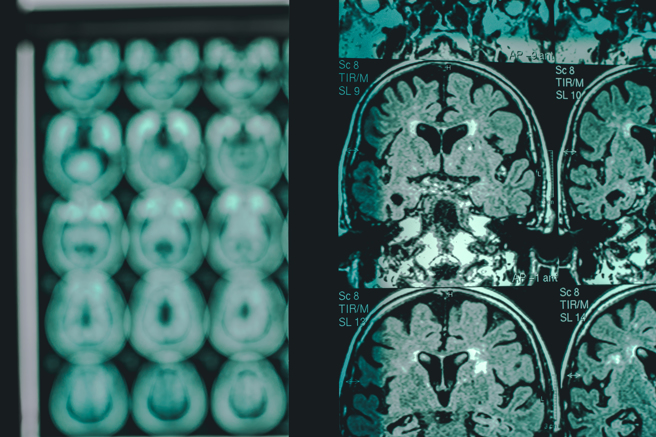

根据这个研究结果推论,除了流感疫苗以外,包括像破伤风、白喉、百日咳、 结核病、带状疱疹等之疫苗都能使罹患失智症的风险降低。如果合併先前有关身体发炎现象会造成大脑长久性损伤,当然也能推论各种体内发炎与阿兹海默症的关联。从研究数据上看,老年人若曾发生呼吸道感染、肺炎、疱疹、牙周病以及新冠肺炎等,他们的认知功能退化的风险也会增高。科学家据此推测,接种预防上述各种疾病的疫苗,能预防因感染这些病症造成的全身性发炎,当然就有延缓或避免认知功能退化的功效,也有助于降低罹患阿兹海默症风险。

这次研究人员也注意到流感疫苗与阿兹海默症风险之间有可能会存在特殊机制,例如流感病毒侵入中枢神经造成损伤,或是免疫反应造成脑神经细胞受损,以及流感引起的併发症与脑损伤之间的关联。当然研究也会往非特殊性机制方向进行,例如杜克大学研究65~75老人接种肺炎球菌疫苗,发现能使罹患阿兹海默症风险降低25%~30%。不过舒兹博士认为,目前还是比较倾向于认为降低阿兹海默症风险的现象并非流感疫苗的特殊效应,而是疫苗的普遍效应。